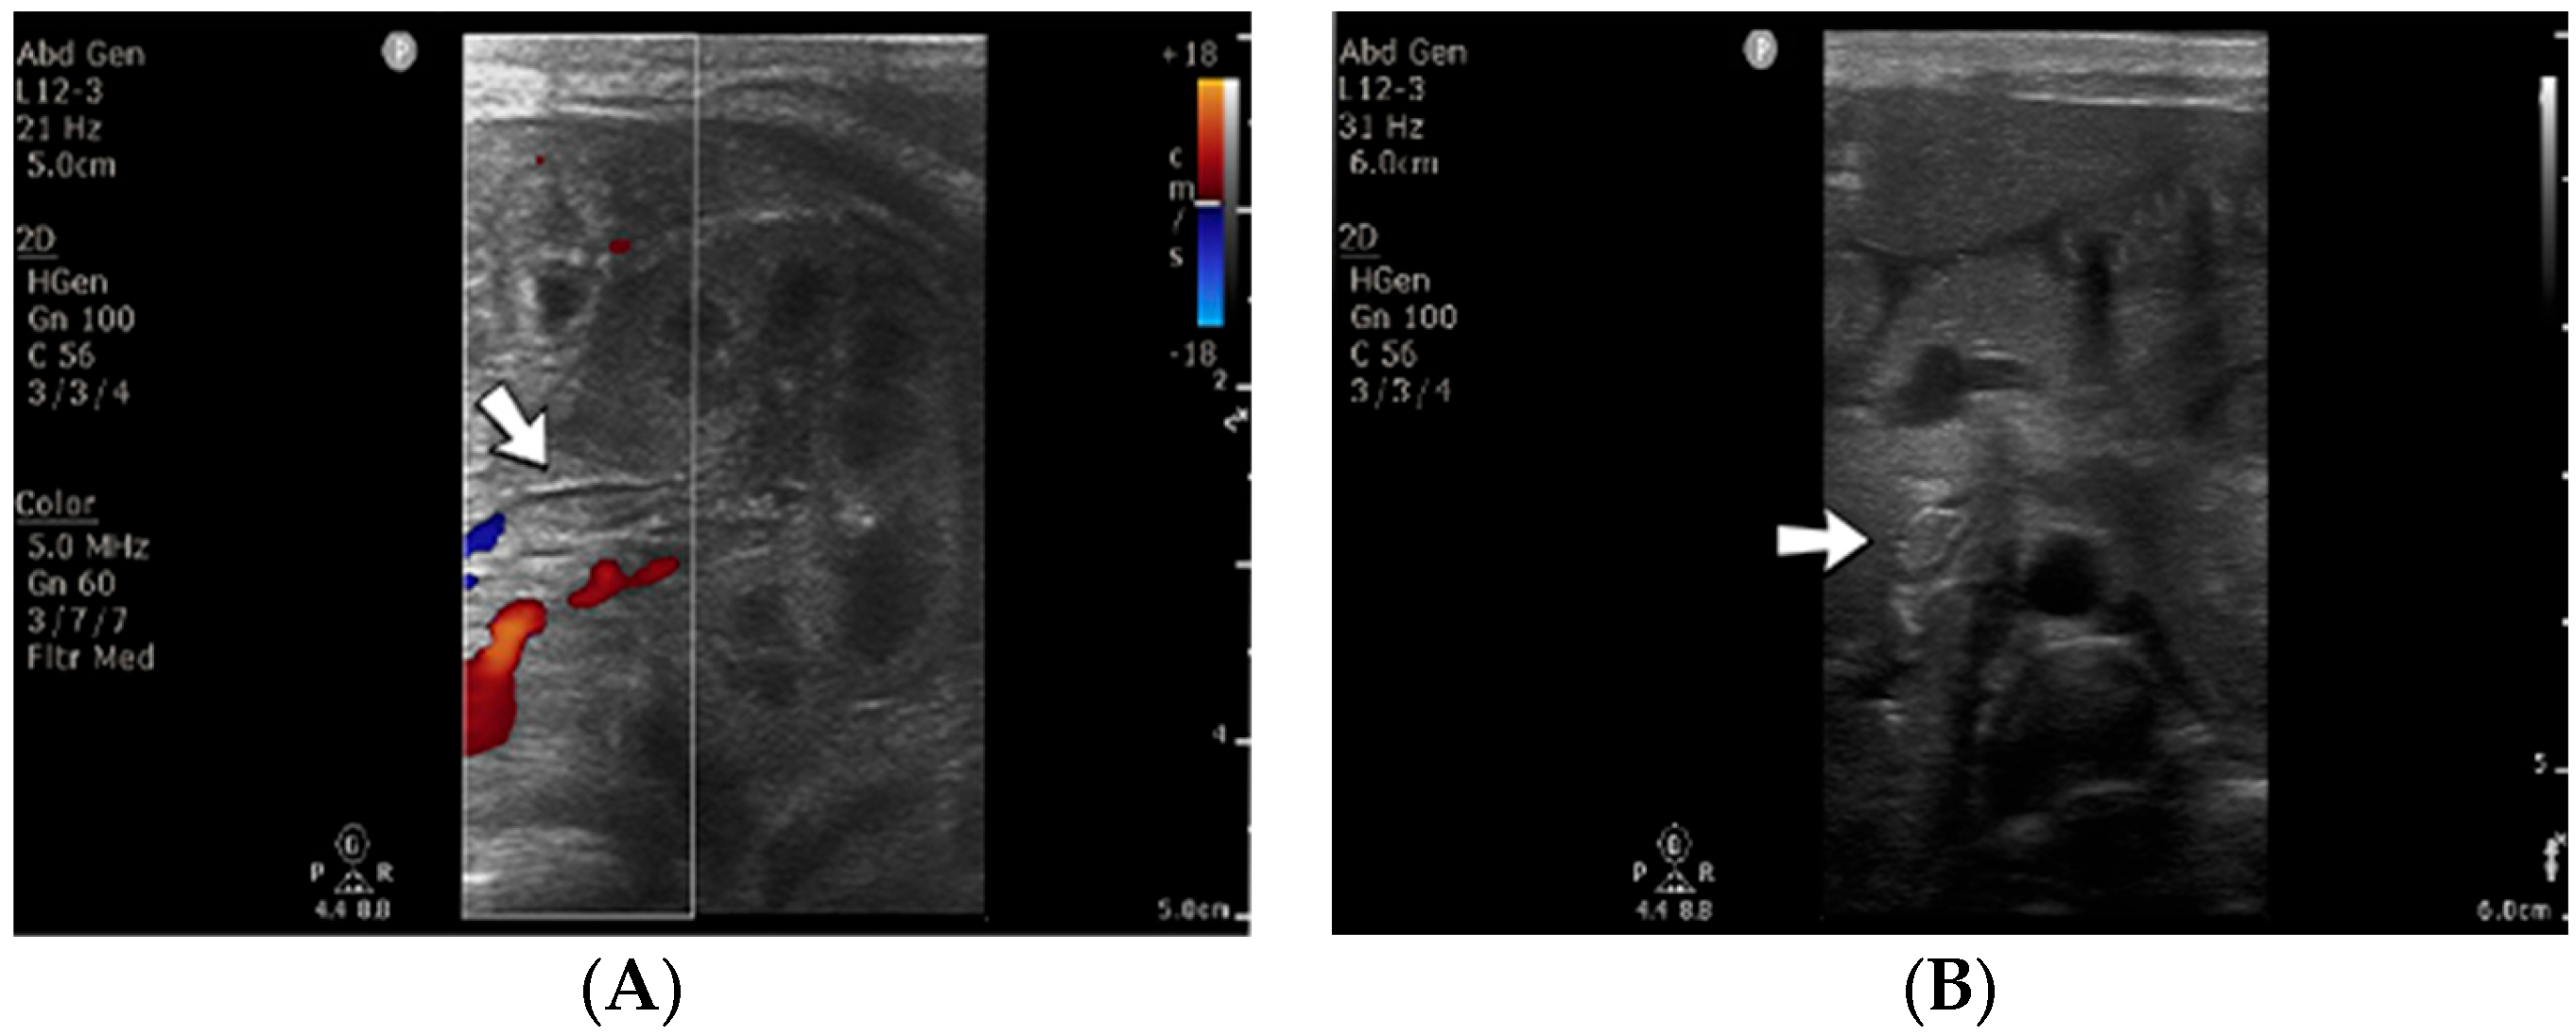

4.29. Case No. 29—Postnatal Thrombosis of the Inferior Vena Cava, Both Renal Veins, the Left Common Iliac Vein

A 3-day-old male neonate (38 weeks, 3 kg) presented with sepsis and acute renal failure, which developed at 48 h of life. The laboratory findings from birth showed mild thrombocytopenia and elevated c-reactive protein. On admission, normal coagulation tests and D-dimer tests were detected. An abdominal ultrasound revealed thrombosis of the inferior vena cava, both renal veins, and the left common iliac vein (Figure 10). Continuous renal replacement therapy was initiated, with continuous heparin infusion for the hemodialysis device. Treatment with bivalirudin was associated for two days, and then switched to alteplase. The D-dimer values increased to undetectable levels.

Figure 10.

Thrombosis of the left renal vein (A) and thrombosis of the inferior vena cava (B) were noticed on abdominal ultrasound. No Doppler signal was identified on the renal vein versus the renal artery (A).

Even though revascularization of the right renal vein was detected on ultrasound after ten days of continuous infusion with alteplase, anuria persisted. Multiple warnings of filter clotting and high transmembrane pressure through the filter were received, which led to several heparin bolus administrations and multiple replacements of the CRRT circuit. The patient died at 20 days of life due to multiorgan failure.

Genetic testing confirmed inherited thrombophilia, with a positive MTHFR A1298C heterozygous gene mutation and Antithrombin, Protein S, and Protein C deficiencies. A moderate elevation of PAI-1 was also detected. There was a positive family history of maternal thrombophilia, one maternal miscarriage, and an older brother known with perinatal stroke.